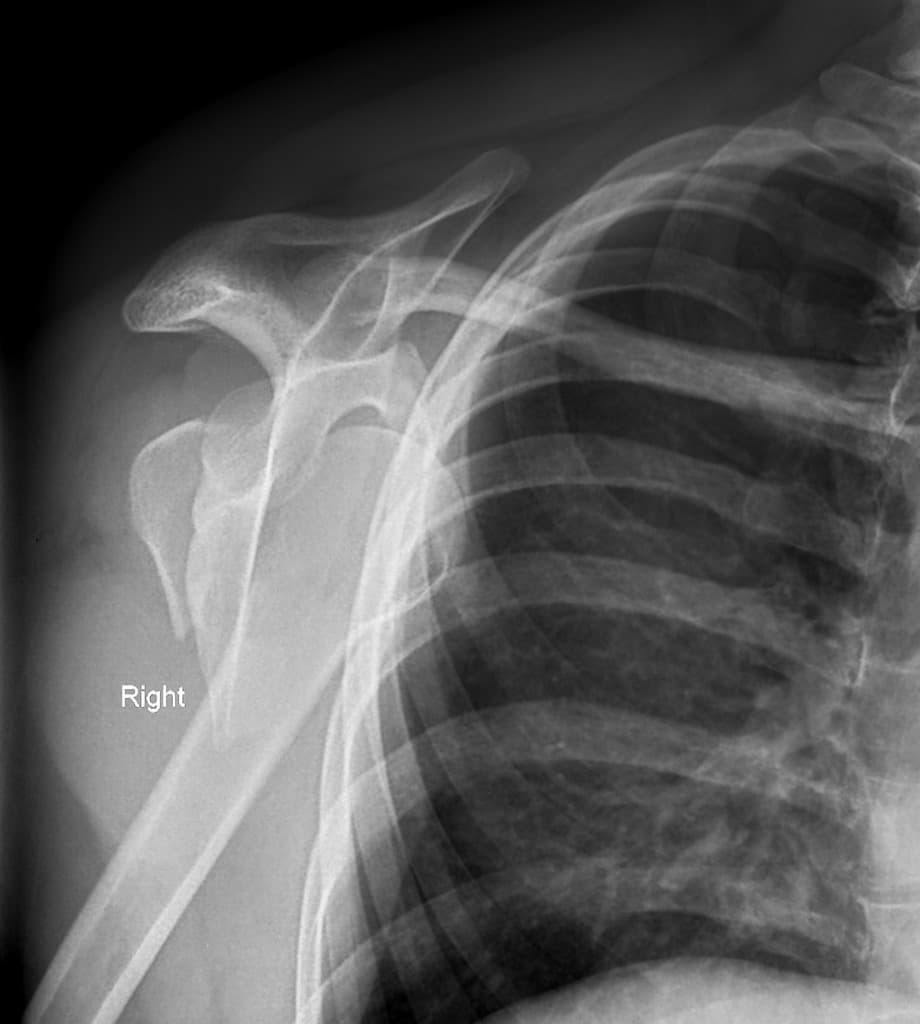

Ca bệnhTrật khớp vai tái phát

Trật khớp vai tái phát

Tiền sử trật khớp tái hồi

Trật khớp vai tái hồi

- "Trật khớp tái hồi thường dẫn đến tổn thương sụn viền và xương."

- "Chụp cộng hưởng từ hoặc CT có tiêm thuốc nội khớp được ưu tiên để đánh giá chi tiết các cấu trúc ổn định."

- "Trật khớp tái hồi thường liên quan đến tổn thương Bankart và Hill-Sachs."

- "Chụp cộng hưởng từ hoặc cắt lớp vi tính có tiêm thuốc nội khớp được ưu tiên để đánh giá các khiếm khuyết sụn viền và xương."

Trật khớp tái hồi thường gặp ở khớp vai, thường là kết quả của một chấn thương ban đầu làm tổn thương các cấu trúc ổn định như sụn viền ổ chảo hoặc bao khớp, dẫn đến tình trạng mất vững mạn tính.